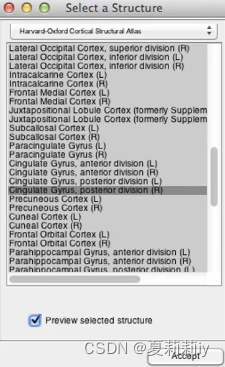

(6)Structure